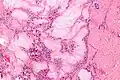

Micrograph of a gouty tophus